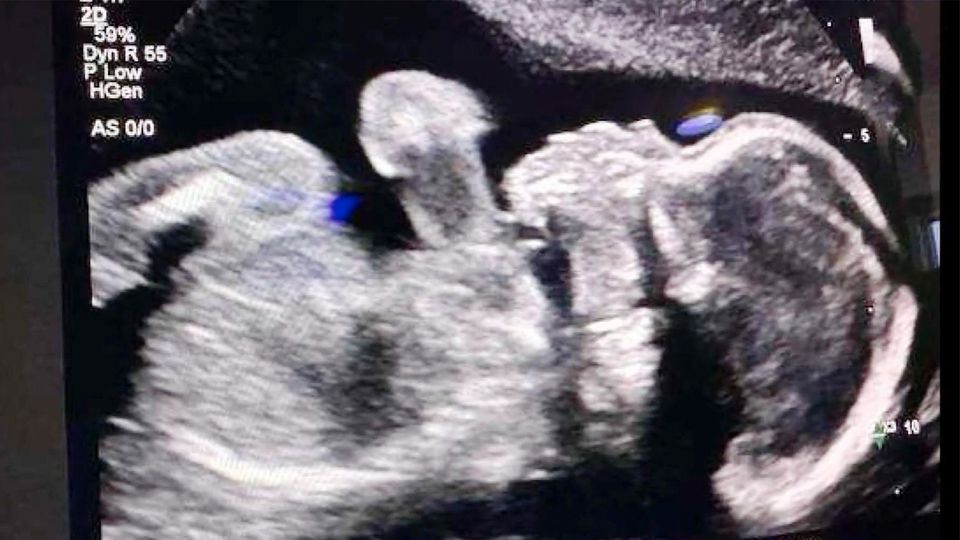

Adriana Smith aus dem US-Bundesstaat Georgia ist hirntot und wird gegen den Willen ihrer Familie am Leben gehalten. Der Grund sind strenge Abtreibungsgesetze in den USA.

US-Abtreibungsgesetz Hirntote Schwangere wird am Leben gehalten – gegen den Willen ihrer Familie